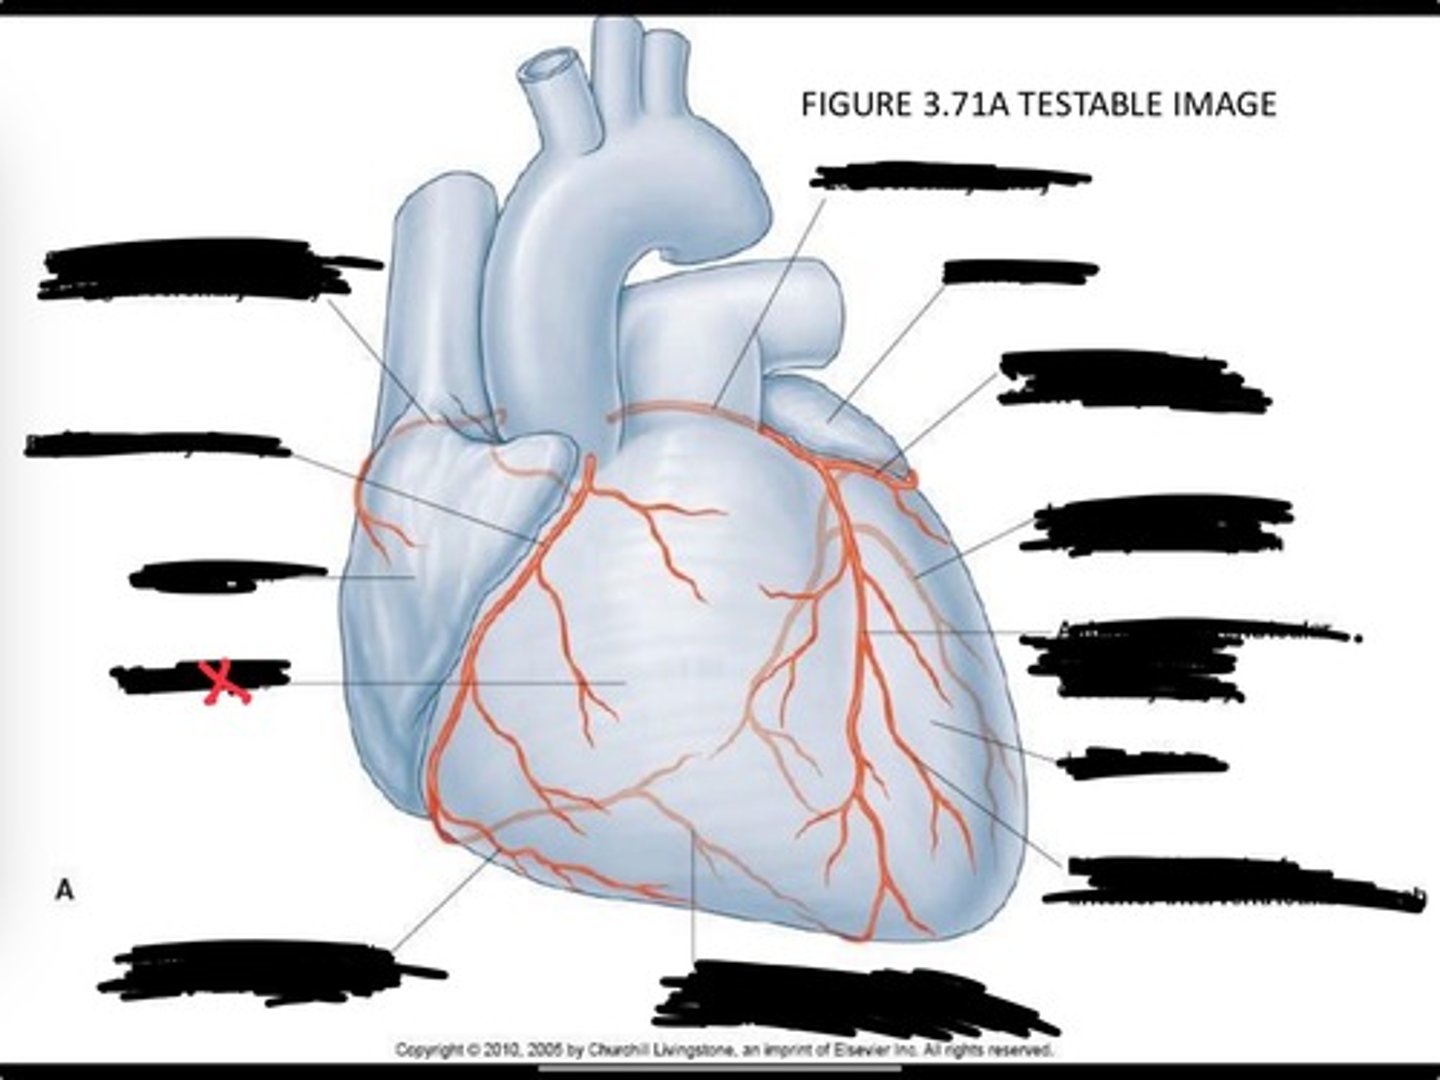

Posterior interventricular branch of right coronary artery

Right arginal branch of coronary artery

Right ventricle

Right atrium

Right coronary artery

Sinu-atrial nodal branch of right coronary artery

Left coronary artery

Left auricle

Circumflex branch of coronary artery